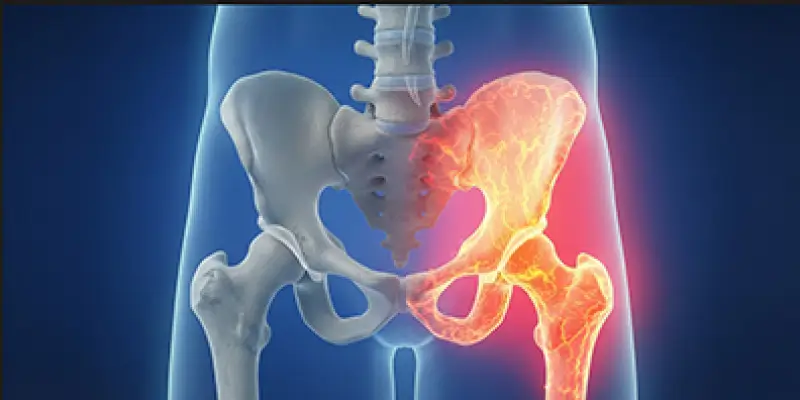

Robotik diz ve kalça protezi, 3D görüntüleme ve robotik rehberlik ile hassas, kişiye özel protez yerleştirmesidir. Avantajlar, endikasyonlar ve rehabilitasyon.

Avasküler nekroz, kemiğe giden kan dolaşımının bozulması sonucu kemik dokusunun canlılığını kaybetmesiyle ortaya çıkan ortopedik hastalıktır. Core decompression tedavisi, belirtileri ve süreci.